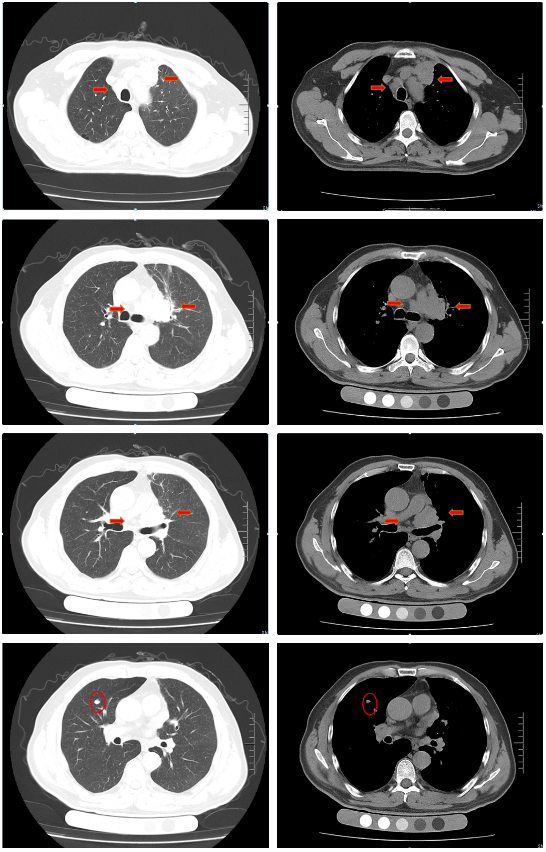

胸部增强CT(2022-02-12):左肺门及纵隔内见团块状软组织密度影,大小约62mm×42mm,边界不规整,内见血管影穿行,增强扫描呈轻度强化,局部支气管狭窄,远端肺内见片状磨玻璃密度影,边界欠清。右肺上叶见结节状密度增高影,较大直径约为8mm,增强扫描呈轻中度强化,右侧斜裂见长径约为6mm的高密度影,增强扫描未见明显强化;两肺透亮度增强,左肺下叶胸膜下囊状透光区。余气管、支气管通畅,未见明显狭窄、阻塞。纵隔和左肺门区见多发肿大淋巴结影,部分融合。两侧胸腔无明显积液。胸部CT诊断:左肺门及纵隔内占位,考虑肺Ca;纵隔及左肺门淋巴结肿大;右肺上叶结节,转移可能;右侧斜裂下结节;两肺肺气肿、左肺下叶肺大泡。

胸部CT(2022-04-12):左肺门及纵隔内见团块状软组织密度影,大小约57mm×37mm,边界不规整,局部支气管狭窄,远端肺内见片状磨玻璃密度影,边界欠清。右肺上叶见结节状密度增高影,较大直径约为9mm,右侧斜裂见长径约为7mm的高密度影;两肺透亮度增强,左肺下叶胸膜下囊状透光区;两肺可见索条状影。余气管、支气管通畅,未见明显狭窄、阻塞。纵隔和左肺门区见多发肿大淋巴结影,部分融合。两侧胸腔无明显积液。胸部CT诊断:左肺占位复查;纵隔及左肺门淋巴结肿大;右肺上叶结节,转移可能;右侧斜裂下结节;两肺肺气肿、左肺下叶肺大泡。

胸部CT(2022-07-15):双侧肺野透亮度增加,以两上肺和胸膜下明显。双肺纹理增多、增粗,紊乱,左肺上叶条片状高密度灶,大小约45mm×19mm,小叶间隔增厚。气管、左右主支气管无明显狭窄。纵隔内未见肿大淋巴结影。两侧胸腔无明显积液。胸部CT诊断:左上肺门占位复查;慢性支气管炎-肺气肿样改变。

治疗后评价:患者经过EP方案联合斯鲁利单抗治疗四周期后,患者咳嗽、咳痰及左侧胸痛症状消失,体重逐渐恢复;影像学提示左肺病灶及纵膈淋巴结及肺门淋巴结较前明显缩小(缩小>30%),右肺结节基本消失;疗效评价:PR(接近CR)。

胸部CT(2022-08-30):双侧肺野透亮度增加,以两上肺和胸膜下明显。双肺纹理增多、增粗,紊乱,左肺上叶见条片状高密度灶,大小29mm×18mm,小叶间隔增厚,两肺下叶见囊状透亮区。气管、左右主支气管无明显狭窄。纵隔内未见肿大淋巴结影。两侧胸腔无明显积液。胸部CT诊断:左上肺门占位复查;慢性支气管炎-肺气肿样改变;两肺下叶肺气肿。

治疗后评价:患者经过斯鲁利单抗单药维持治疗两周期后,患者未再出现咳嗽等症状,体重逐渐增加。影像学提示左肺病灶及纵隔淋巴结及肺门淋巴结、右肺结节基本消失,疗效评价接近CR。